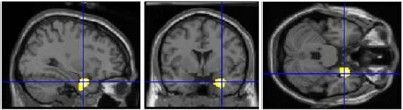

1) canonical sculptures activated right insula (mediates emotions; connects to/from amygdala): evidence for _________ beauty (“I can see why people like that.”)

right insula activity

2) beautiful images activated right amygdala (responds to learned emotional information): evidence for __________ beauty (“I like that.”)

right amygdala activity

- conclusion: both of these non-mutually exclusive processes contribute to appreciation of artwork